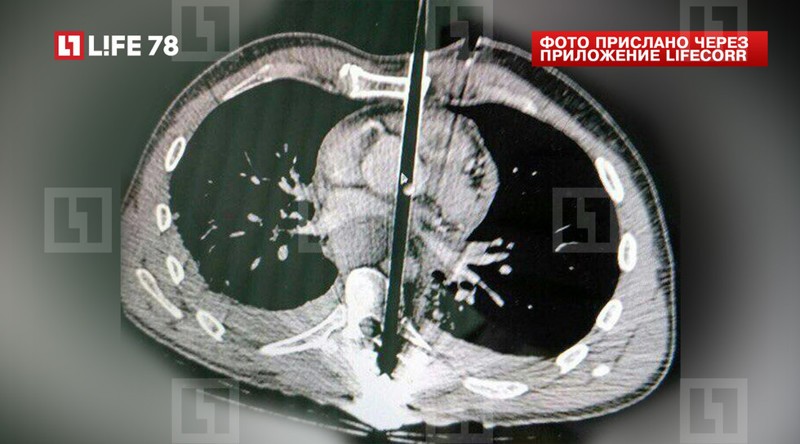

Карета доставила мужчину в приёмный покой Елизаветинской больницы, где ему сделали компьютерную томограмму: один арбалетный болт прошёл через левый желудочек и митральный клапан в левое предсердие, второй — через брюшную аорту.